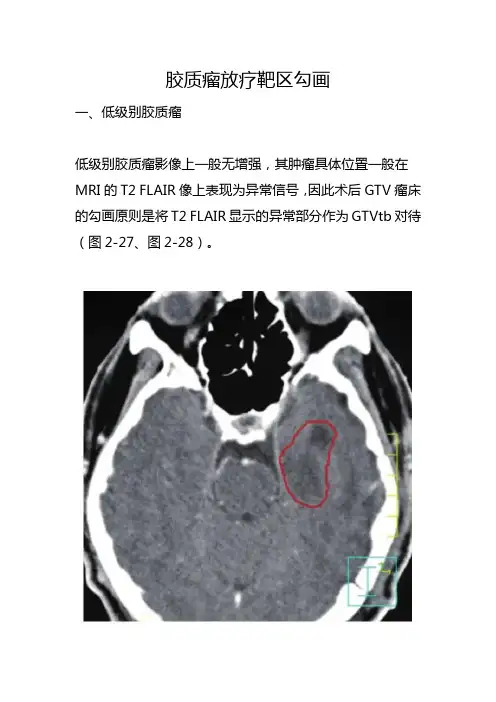

胶质瘤放疗靶区勾画一、低级别胶质瘤低级别胶质瘤影像上一般无增强,其肿瘤具体位置一般在MRI的T2 FLAIR像上表现为异常信号,因此术后GTV瘤床的勾画原则是将T2 FLAIR显示的异常部分作为GTVtb对待(图2-27、图2-28)。

增强CT仅见左侧颞叶术后低密度区FLAIR显示的异常信号大于术腔图2-27 Ⅱ级星形细胞瘤术后GTVtb(红线)以包括FLAIR 显示的异常信号为原则图2-28 少突胶质瘤(Ⅱ级)术后GTVtb(红线)的勾画以T2 FLAIR显示的异常信号为原则,黄线为外扩1.5cm的CTV而CTV一般根据分化程度而有所不同:病理分化为Ⅰ级者,CTV=GTV+1cm(即在GTV基础上外放1.0cm)。